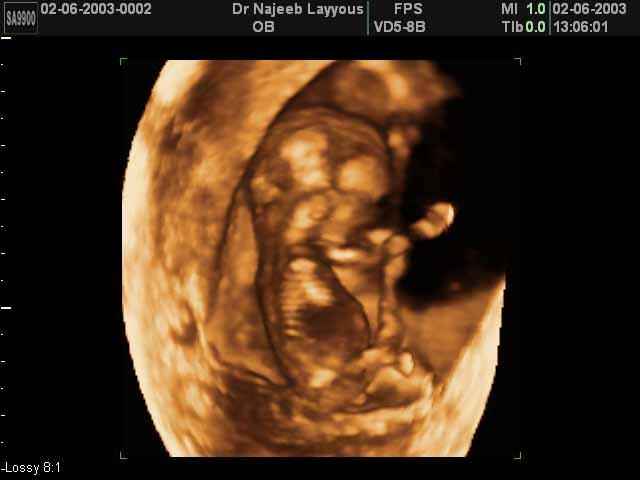

3D First Trimester Ultrasound Scan Photos